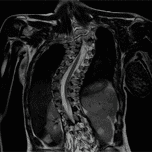

我們是一家位於西班牙巴塞隆納的國際專科醫療中心,不設分院,專注於精準且高品質的醫療照護。我們採用微創手術從病因治療Arnold-Chiari I型症候群、特發性脊髓空洞症與脊柱側彎等相關疾病,致力於為來自世界各地的患者帶來更安全、更有效的治療選擇。